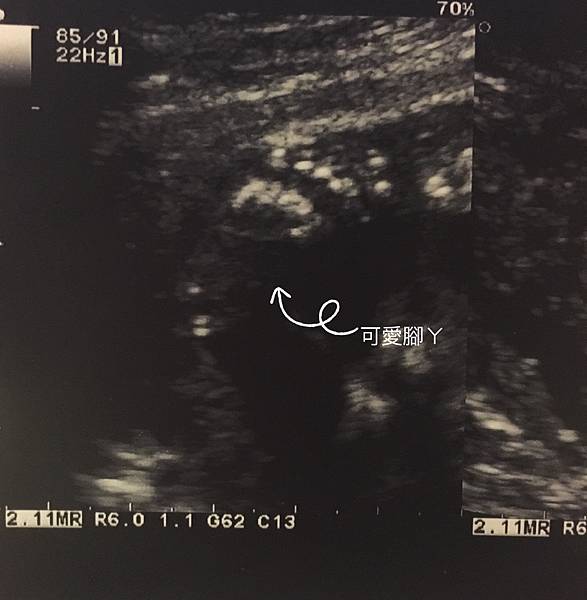

董醫師照超音波非常細心,會告訴你這是哪裡哪裡

還有數手指頭,反而是我常常聽到放空(這位媽媽這樣對嗎)

看到小寶貝的小手小腳覺得天啊太可愛了![]()